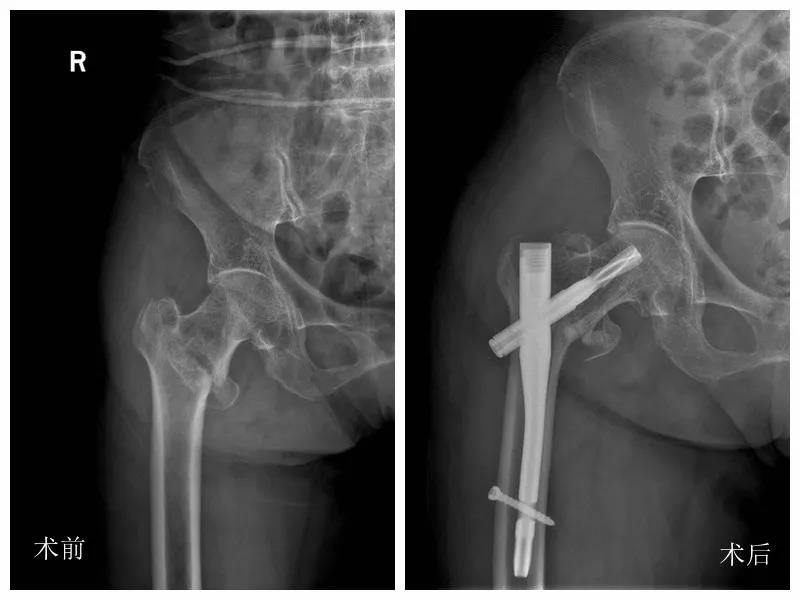

然而,在鄞州二院却迎来了3位“80、90后”的股骨粗隆骨折患者。

这些“80、90后”可不是那些生龙活虎的小鲜肉,而是真正的80岁、90岁以上高龄的老年患者。

该院急救医学中心李之斌副主任介绍,老年髋部骨折是骨质疏松性骨折中的一种常见且严重类型,致死、致残率高,医疗花费大。跌倒是导致老年髋部骨折的主要因素。跌倒可能是某一个因素直接导致的,但通常是由多个危险因素相互作用造成的,包括气候、环境因素、生理因素和神经骨骼肌肉系统因素等。

而去年一个冬天,该院就救治了20例80岁以上股骨粗隆骨折病患。